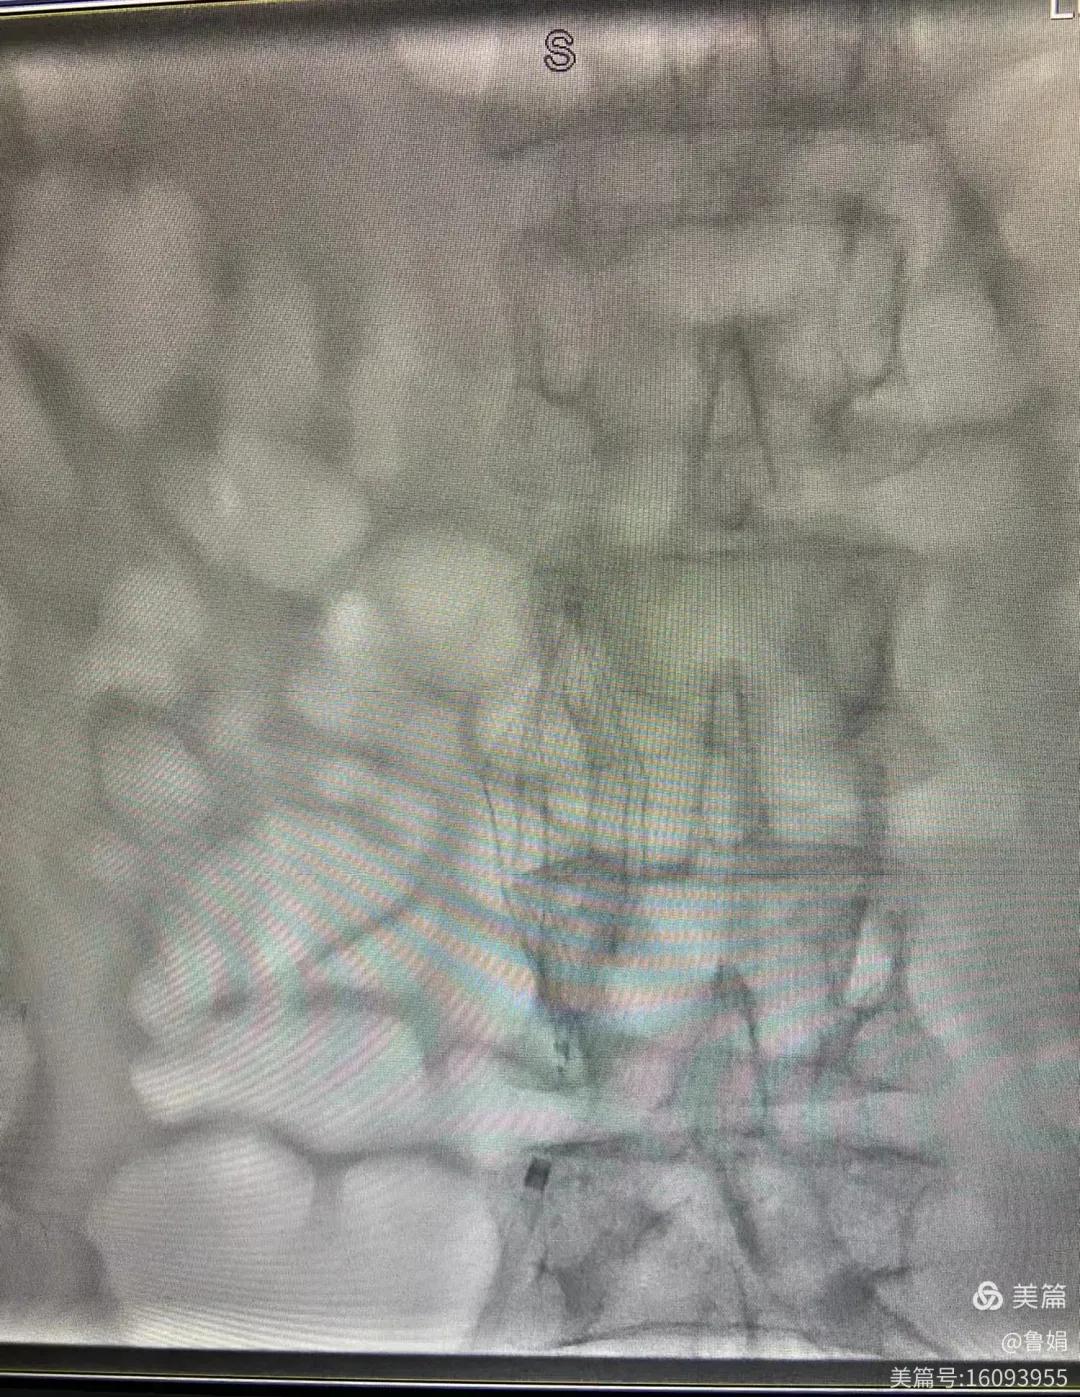

圖片術(shù)后濾器順利植入

經(jīng)認(rèn)真查看患者病例,探討患者病情及術(shù)中潛在風(fēng)險(xiǎn)因素,多科會(huì)診后急診為患者開展介入手術(shù),術(shù)中周創(chuàng)業(yè)副主任、孫亞中副主任中醫(yī)師二人通力合作,手術(shù)順利,病人術(shù)中出血少,生命體征平穩(wěn),現(xiàn)在腦二科病房繼續(xù)對(duì)癥治療。(介入中心:魯娟)